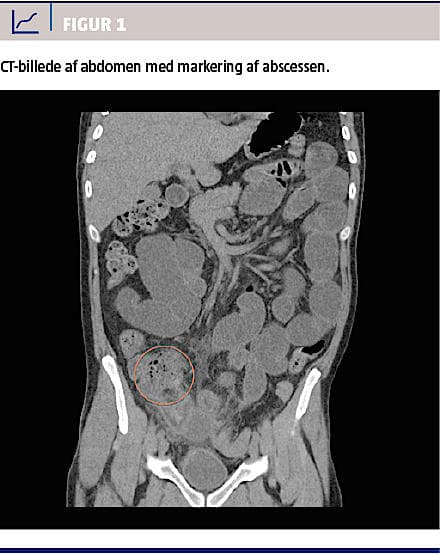

En 34-årig mand, der havde paranoid skizofreni og boede på et socialpsykiatrisk botilbud, blev pga. flere dages mavesmerter indlagt på en somatisk afdeling. Man fandt en øm udfyldning i højre fossa, men ingen peritoneal reaktion. Patienten var septisk. På mistanke om abdominal infektion foretog man en akut CT af abdomen, hvor der blev påvist en periappendikulær absces, der målte 4,6 × 9,3 cm og strakte sig ned bag blæren og ned mod fossa vesico rectalis (Figur 1). Man bemærkede, at abscessen sad svært, men dog tilgængelig for drænage og fandt indikation for at foretage proceduren. Patienten blev gentagne gange informeret om tilstandens potentielle farlighed, og af bl.a. tilkaldt personale fra botilbuddet, forsøgte man at motivere ham til at lade sig behandle som anbefalet. Han accepterede fortsat frivillig indlæggelse, men frabad sig nogen form for kirurgisk behandling. Han gav dog samtykke til behandling med relevant intravenøst givet antibiotika.